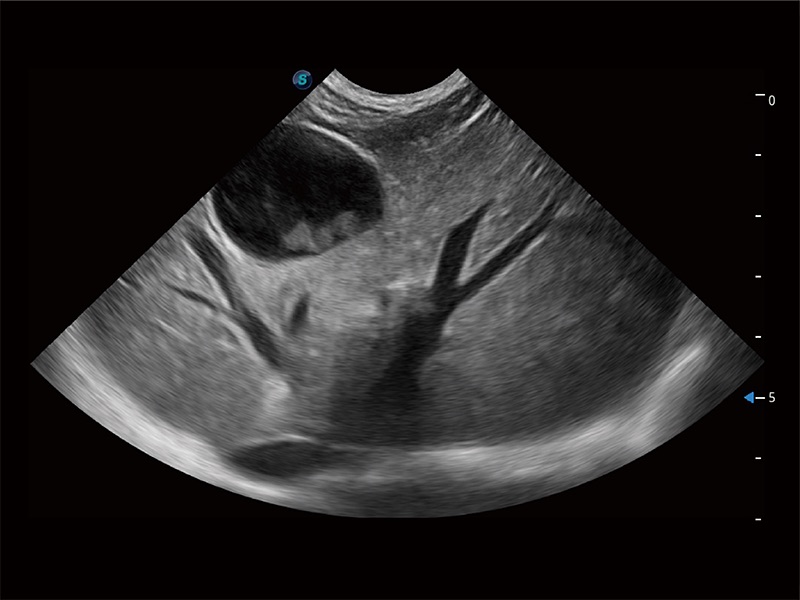

ProPet 80 配备了丰富的心脏探头群、先进的成像技术和专业的心脏测量工具,可帮助动物医生为不同体型和生理结构的动物提供心脏和心肌功能的全面评估。

通过360度任意调节3条M型取样线,在同一心动周期上观察心脏不同位置的运动曲线,得到准确的心功能测量数据,有效评估心肌运动及左心室功能。